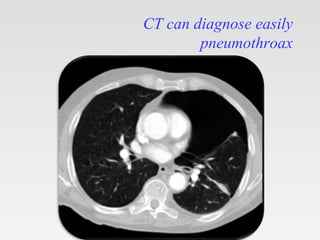

CT scanning

It is recommended in difficult cases such

as patients in whom the lungs are

obscured by overlying surgical

emphysema

To differentiate a pneumothorax from

suspected bulla in complex cystic lung

disease

CT can diagnose easily

pneumothroax